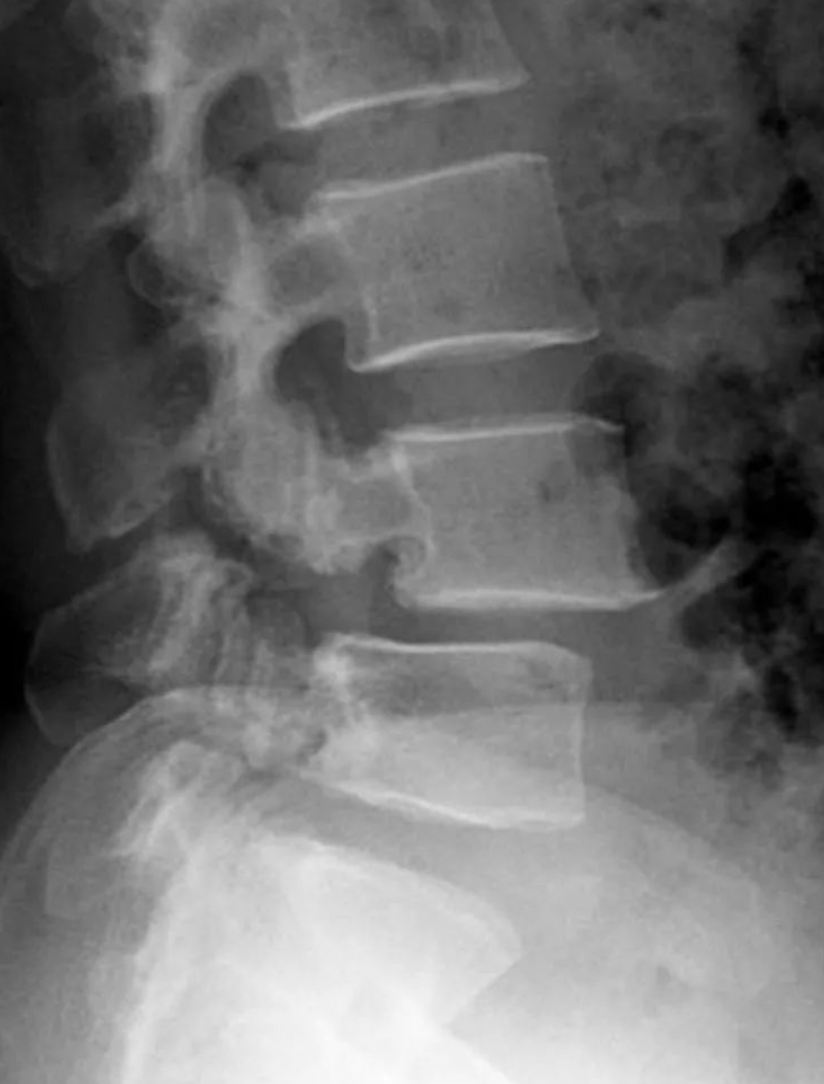

腰4椎弓峡部裂,腰4椎体向前滑脱,程度为I度。

II度滑脱。

辑:腰4椎弓峡部裂,腰4椎体向前II度滑脱。